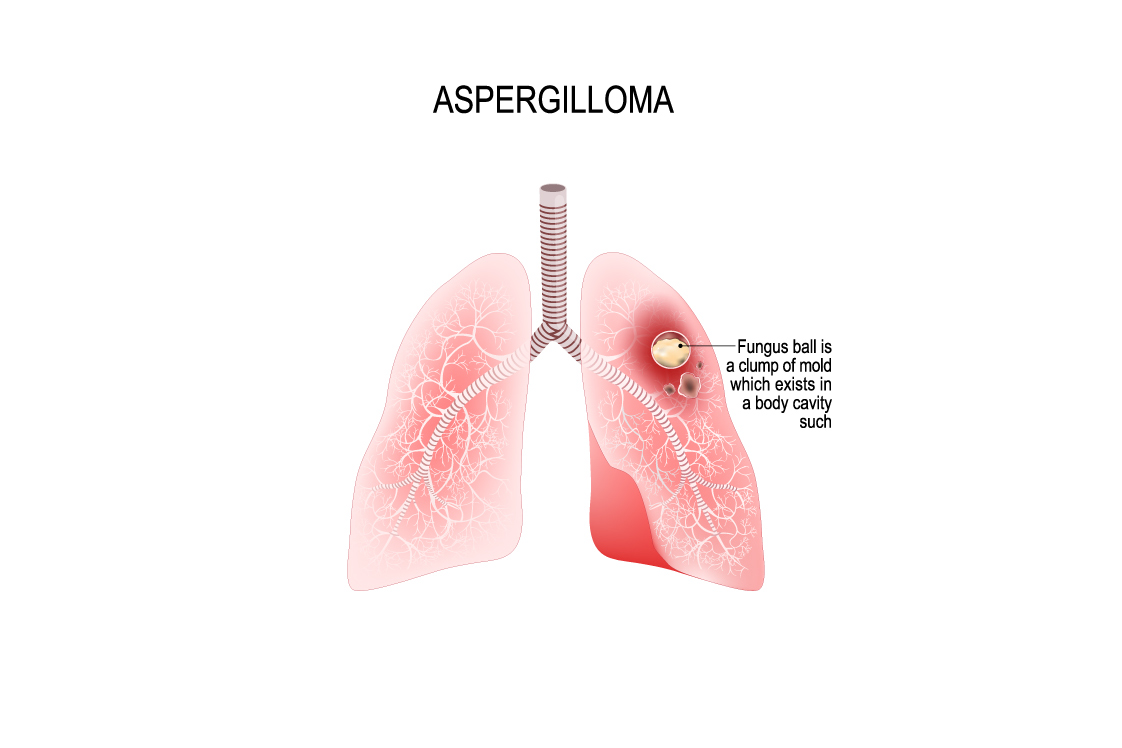

肺アスペルギルス症

アスペルギルス(真菌の種類)による肺真菌症は、侵襲性、慢性、単純性、アレルギー性の4つのタイプに大別されます。これらは、それぞれ異なる基礎疾患、経過、治療法を持っており、正確な診断と適切な治療が重要です。